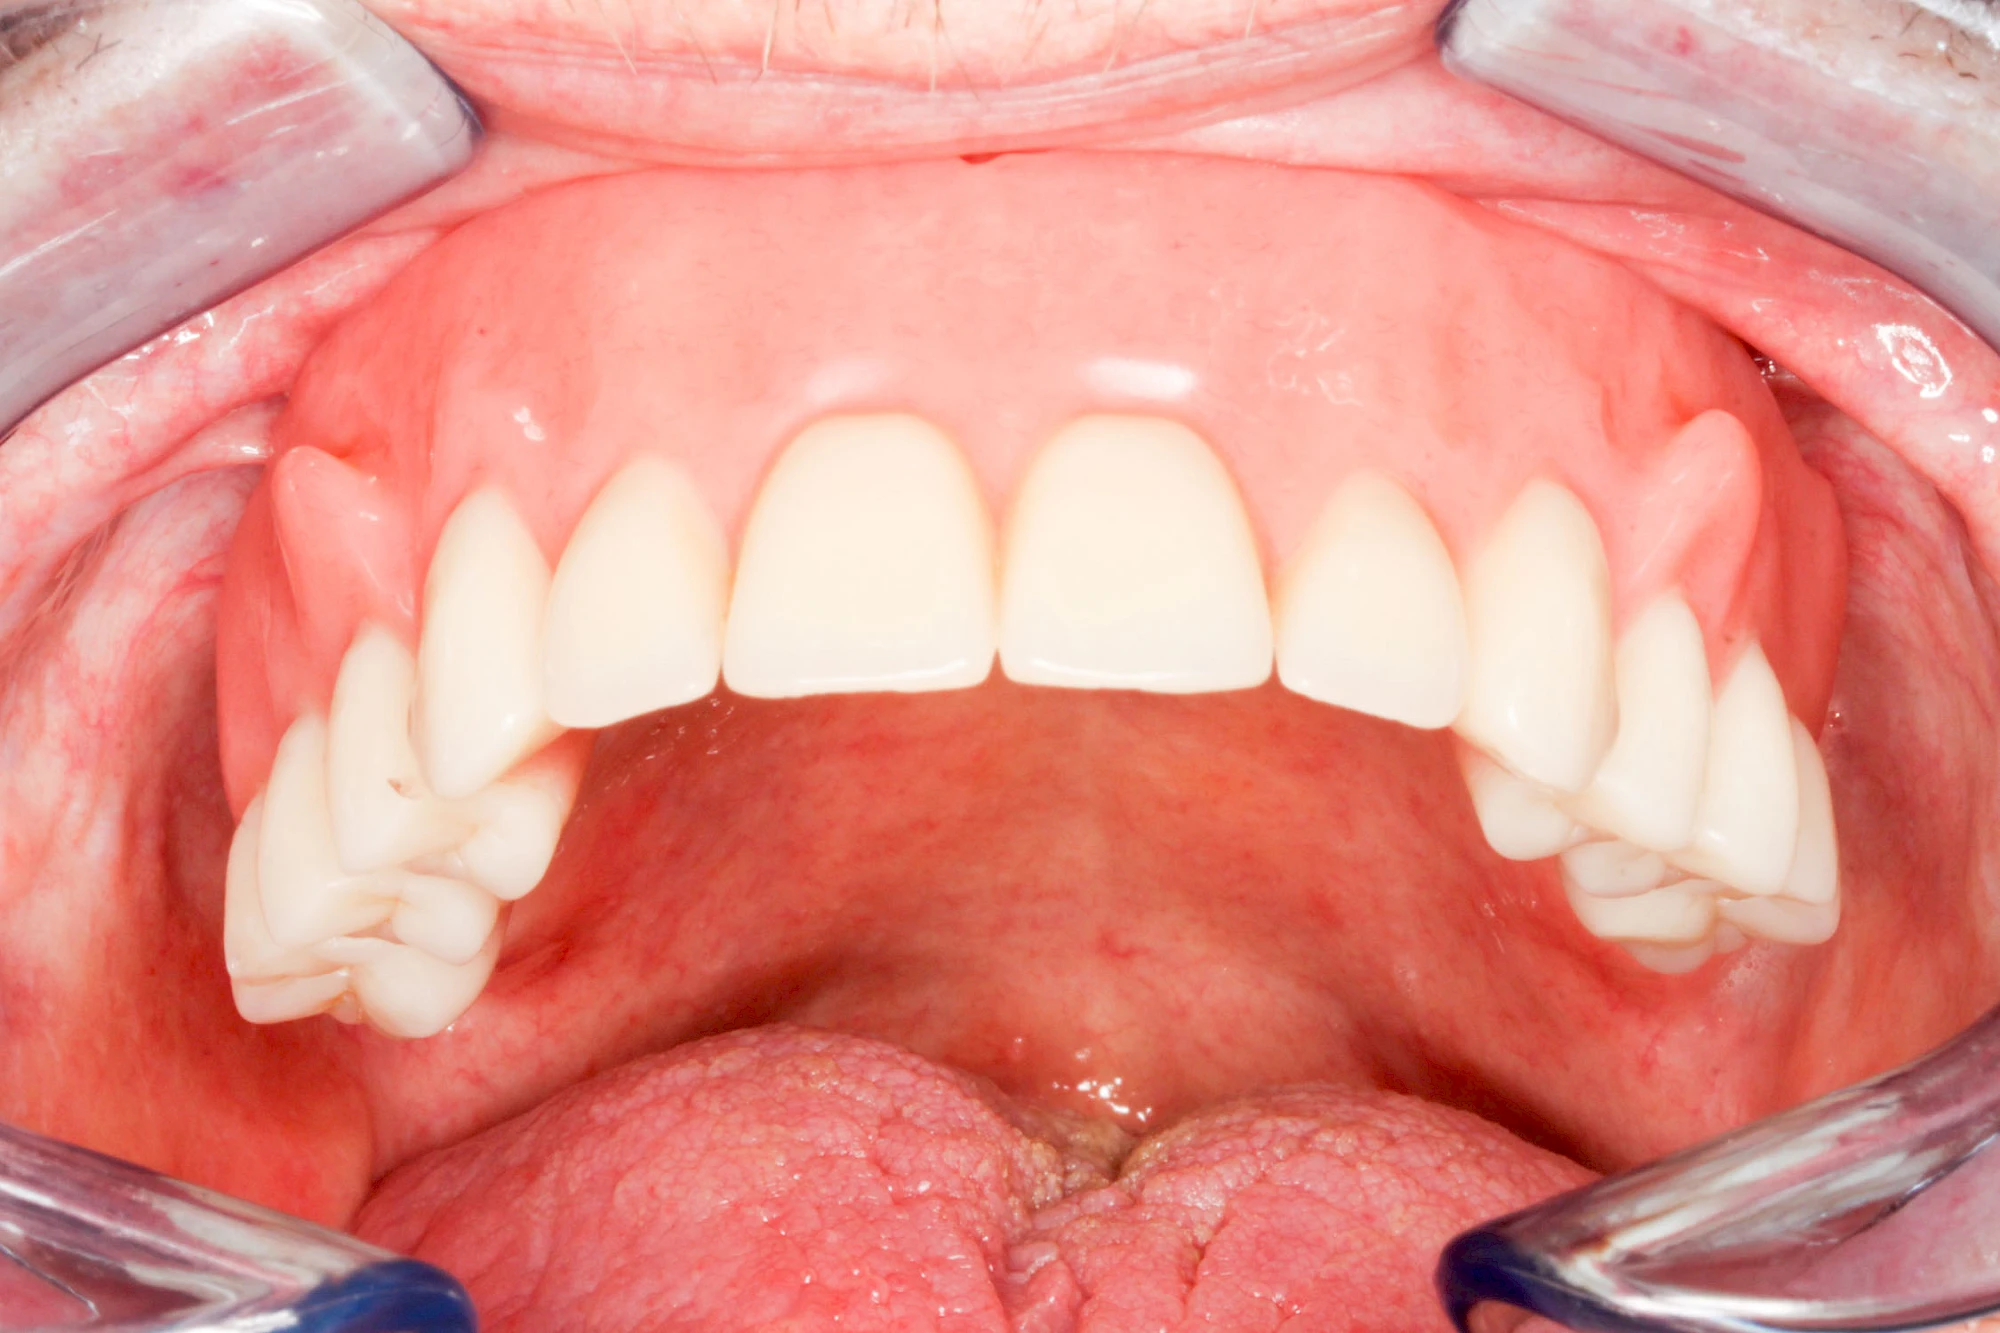

Fehlen einzelne Zähne und die Nachbarzähne sind unbeschadet oder gut zahnärztlich versorgt, werden immer häufiger Implantate gewählt, um die Lücken zu schließen. Auch bei größeren oder verteilten Lücken, wenn keine herausnehmbare Prothese gewünscht ist, werden Implantate für Kronen- bzw. Brückenversorgungen gesetzt. In Einzelfällen entscheiden sich sogar zahnlose Patienten für eine festsitzende Versorgung auf Implantaten.